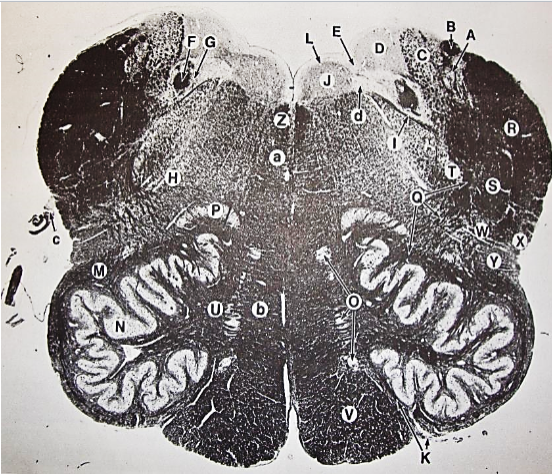

A

posterior median sulcus

B

posterior intermediate sulcus

C

anterior median fissure

D

gracile fasciculus

E

Gracile nucleus

F

fasciculus cuneatus

G

spinal trigeminal tract

H+I collectively

spinal trigeminal nucleus

J

Accessory nucleus

K

pyramidal decussation

L

lateral corticospinal tract

M

rubrospinal tract

N

posterior spinocerebellar tract

O

anterior spinocerebellar tract

P

lateral spinothalamic tract

Q

anterior spinothalamic tract

R

lateral vestibulospinal tract

S

medial longitudinal fasciculus

T

tectospinal tract

U

central canal

A

fasciculus gracilis

B

gracile nucleus

C

fasciculus cuneatus

D

cuneate nucleus

F

internal arcuate fibers

G

decussation of internal arcuate fibers

H

medial lemniscus

I

hypoglossal nucleus

J

dorsal motor nucleus vagus

K

solitary fasciculus

L

solitary nucleus

M

dorsal longitudinal fasciculus

N

spinal trigeminal tract

O

spinal trigeminal nucleus

P

posterior spinocerebellar tract

Q

anterior spinocerebellar tract

R

spinal lemniscus

S

lateral vestibulospinal tract

T

rubrospinal tract

U

lateral reticular nucleus

V

medial accessary olivary nucleus

W

pyramidal (corticospinal) tract

X

arcuate nucelus

Y

medial longitudinal fasciculus

Z

tectospinal tract

a

fascicles of hypoglossal nerve